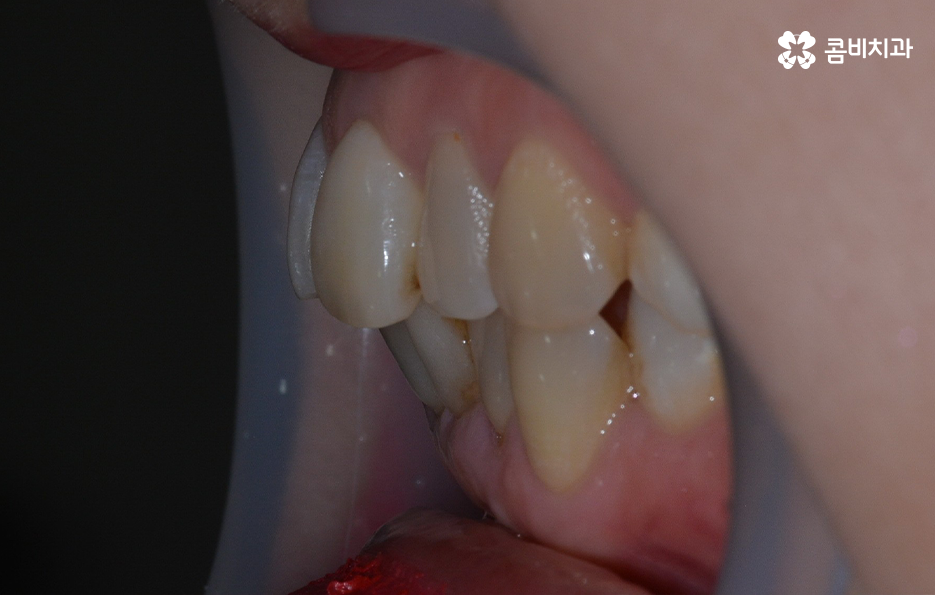

오늘 보시는 교정 사례의 경우를 보시면 아랫니의 틀어짐도 크지만 측면 사진으로 보시면 치열로 인해 돌출입에 영향을 준다는 사실도 알 수 있어요. 즉 치열과 함께 돌출입도 함께 고치고 싶어하기 때문에 치열도 재배열 하지만 치아 안쪽으로 넣어서 입술라인과 얼굴형으로 볼 때도 돌출입도 치료하는 치료 계획을 세웠기 때문에 작은 어금니 발치를 통한 치아의 이동 공간을 확보한 사례로 볼 수 있어요